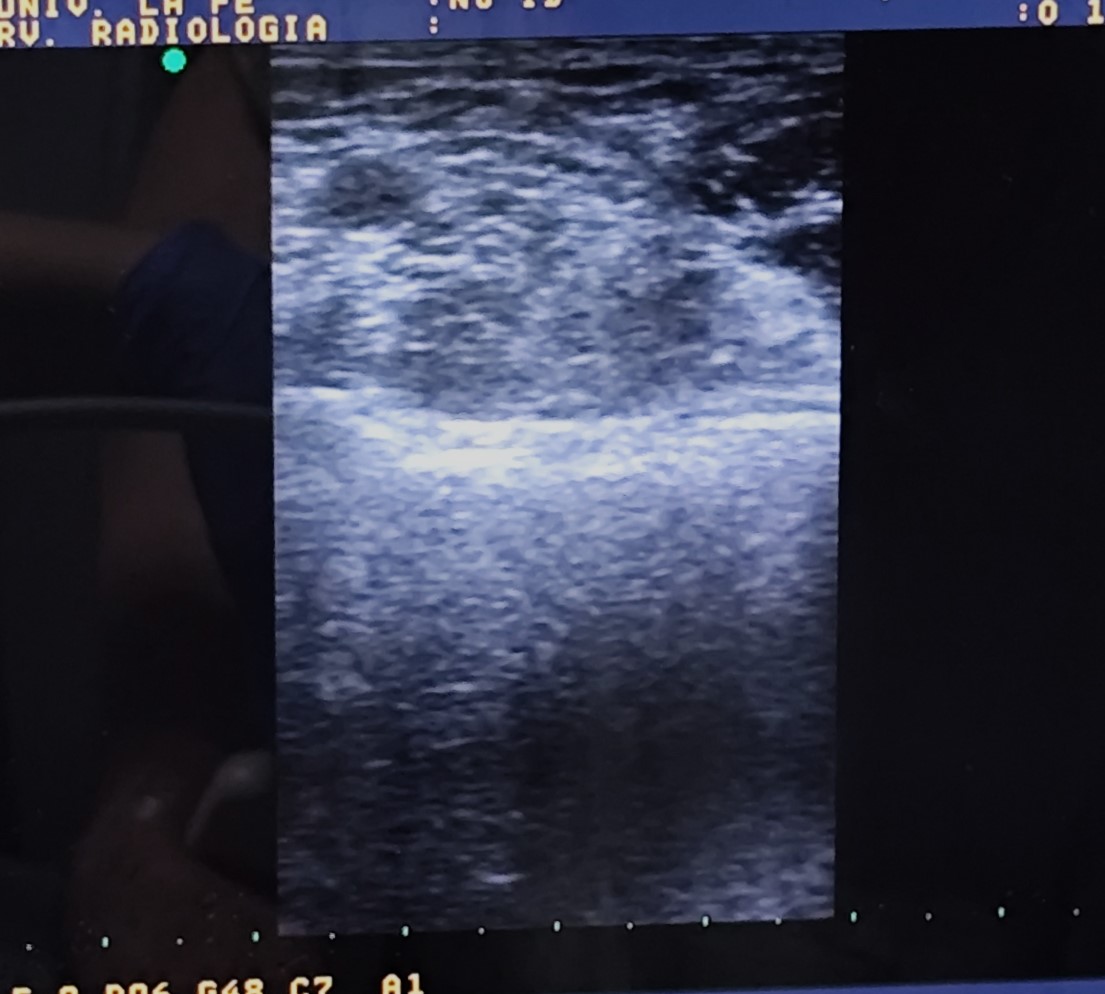

Hombre de 68 años que consulta por lesión quística/nodular en codo izquierdo de varios años de evolución con incremento de molestias al roce y apoyo en las últimas semanas. Sin otra sintomatología por aparatos ni otras articulaciones afectas.

Descripción de los hallazgos ecográficos y las imágenes más relevantes para la resolución del caso

La gota es una enfermedad metabólica crónica que causa depósitos de cristales de urato en tejidos blandos y articulaciones; este caso clínico ilustra un ejemplo, donde un tofo nodular en el codo se convierte en el motivo principal de consulta. La ecografía clínica permitió detectar las características típicas de dicha enfermedad, facilitando un diagnóstico presuntivo sólido y guiando de forma adecuada las decisiones terapéuticas.